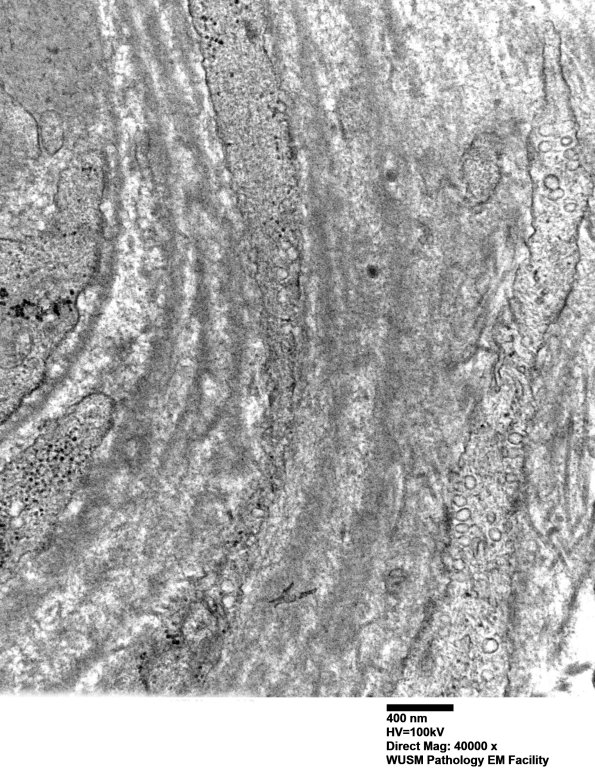

In this vessel the expansion of the vessel wall is largely composed of reduplicated intact and fragmented basal lamina. (electron micrographs) ---- Interpretation: Immune microvasculopathic neuropathy (HIEM), is a diagnosis based on the variable but compelling C5b-9 staining of endoneurial microvessels. ---- Not shown: C5b-9 shows variable staining of endoneurial capillaries establishing the diagnosis of HIEM..